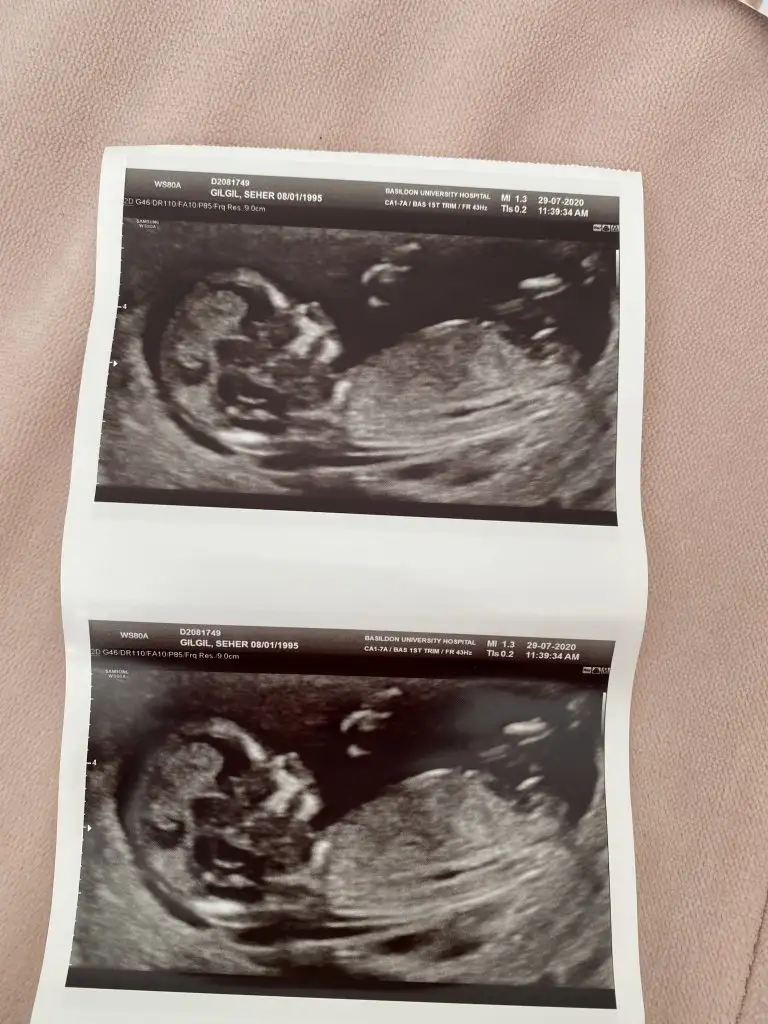

Kız sanki ama nubu ne dik nede paralel poposu yukarı olduğu için etkilemiyorsa kız gibi gibi baska USG de paylaşınCnm arkadaşımın bebeğini yorumlarmısınIkra meyra

Net değil USG 11-12-13. Hafta olmalıEki Görüntüle 2668963 Merhaba, ben kız diye düşündüm ama sizce nedir?

Teşekkür ederim cnm haftaya tekrar gidecek yine atarım resim .Yorum için teşekkürler :) bu gün benimde randevum var :) :)Kız sanki ama nubu ne dik nede paralel poposu yukarı olduğu için etkilemiyorsa kız gibi gibi baska USG de paylaşın

Nubu kız gibi görüntüsü erkek gibi

Kız gibi emin olamadım

Başka USG varmı nub kız görünüyor ama emin olamadım ne dik nede paralel iniyor tam karşıya bakıyor cnmYok cnm ya ben yurt dışındayım 20 haftalıkken söylüyorlar burda ondan çok sabırsızlanıyorum